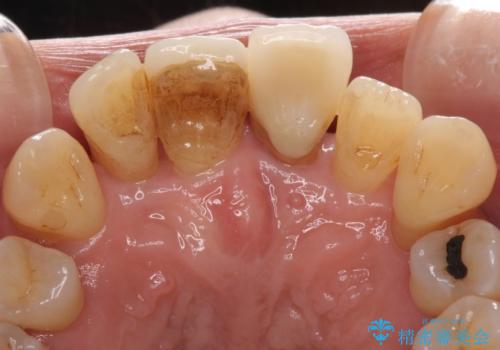

歯周病でグラグラの歯 矯正治療と歯周外科を併用した総合歯科治療

診察を行ったところ、重度歯周病の状態の上に上下の歯列が著しい叢生という状態でした。

歯周初期治療として抜歯や歯槽骨再生治療を行い、さらに歯周ポケット除去を行った後に矯正治療で歯列を整えて行くこととしました。